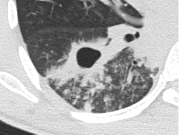

これは活動性の(現在進行形の)肺結核の患者さんのCT画像です。 一見してわかる大きな特徴が2つあります。

1) 肺に「穴」が開いている(空洞)

画像の真ん中にある黒くぽっかり空いた部分、これが「結核の空洞」です。 結核菌が肺の中で増殖し、肺の組織を破壊して(溶かして)しまった跡です。溶けた組織や菌は、咳や痰として体の外へ出されます。その結果、このように肺に穴が開いてしまいます。

2) 菌が「飛び火」している

穴の周りに、白い小さな粒々や線が散らばっているのが見えます。 これは、空洞から溢れ出た結核菌が、気管支を通って別の場所へ飛び火し、炎症を広げている様子です(専門的には「散布」といいます)。

【この画像が意味すること】

このように「空洞」ができている状態は、**「咳や痰の中にたくさんの結核菌が出ている(排菌している)」**可能性が非常に高い状態です。 つまり、周りの人にうつしてしまう力が強いということです。